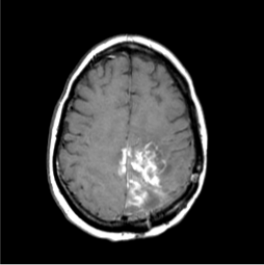

What is the pathology shown in these images?

What is the best weighting to view MS lesions?

What can be seen in this scan?

[EXTRA? Possible MCQ]